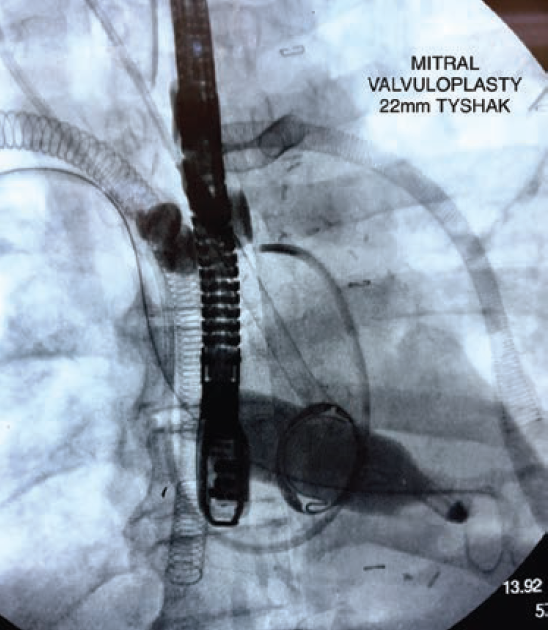

We present a case of a 57-year-old male who underwent bioprosthetic mitral valve replacement (MVR) and developed postoperative cardiogenic shock requiring venoarterial extracorporeal membrane oxygenation (VA ECMO) and Impella 5.5 hemodynamic support. After 14 days on VA ECMO, echocardiography revealed complete fusion of the bioprosthetic mitral valve leaflets. The patient was successfully treated with balloon valvuloplasty with direct access through the right superior pulmonary vein, resulting in improvement in valve function and avoidance of repeat surgery. This case demonstrates the feasibility and efficacy of balloon valvuloplasty as a treatment option for early bioprosthetic valve dysfunction in high-risk patients.

Read the full case from Casazza et al, previously published in Cath Lab Digest’s April 2024 issue